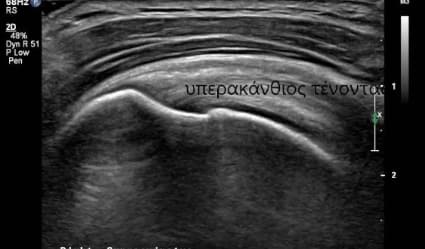

Υπέρηχος μαλακών μορίων

Ο υπερηχοφραφικός έλεγχος διενεργείται με έγχρωμο υπέρηχο τελευταίας γενιάς (ugeo samsung), με τρίπλεξ, ντόπλερ, ελαστογραφία για διάγνωση παθήσεων μυών, φλεγμονές, κυστικές συλλογές...